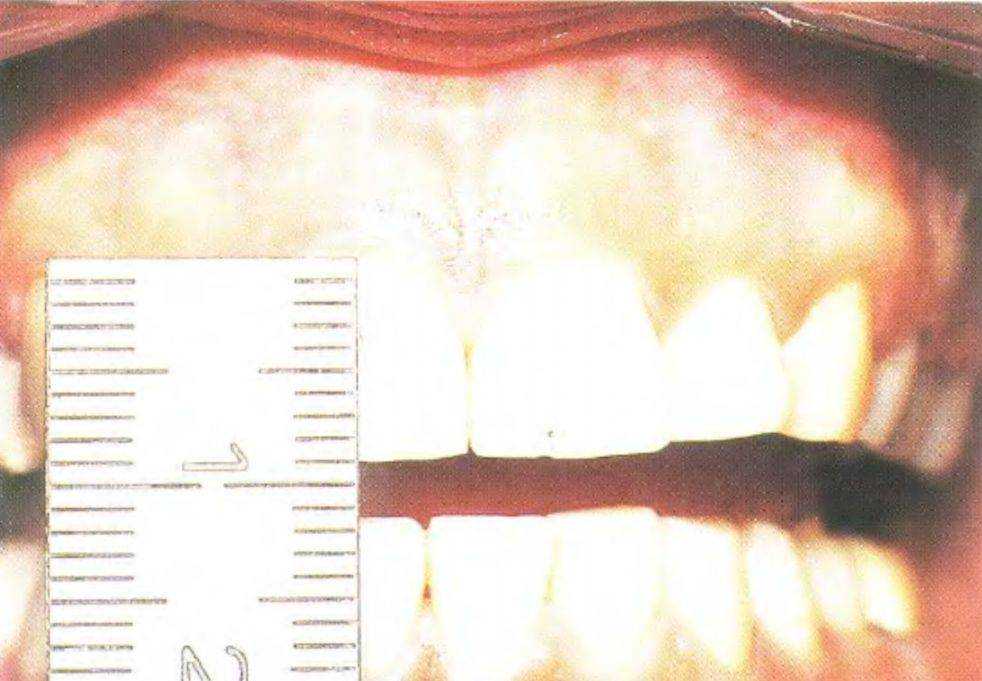

Рис. 3-38с. У пациентки эксцентричный бруксизм

Рис. 3-38е. Привычное межбугорковое положение

Рис. 3-38f. Центральное положение, выбранное пациенткой (психологическая контактная позиция)